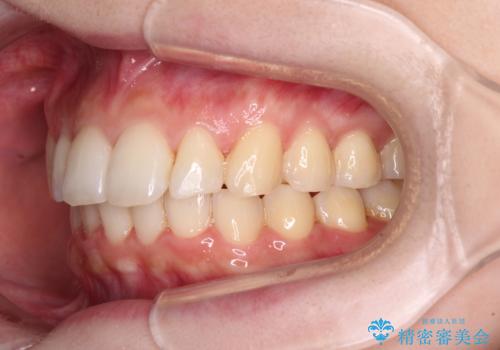

- 30代女性

- 矯正装置

- 審美装置

- 上の前歯が出っ張っている気がするとのことで来院された患者様です。